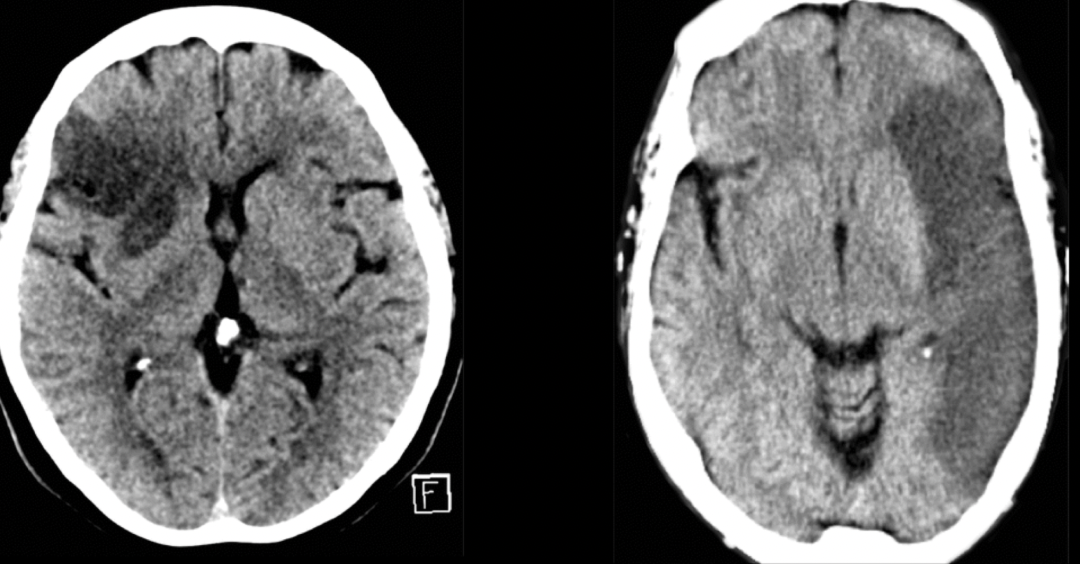

13

Q

Diagnóstico:

A

EVC isquémico en fase hiperaguda

14

Diagnóstico